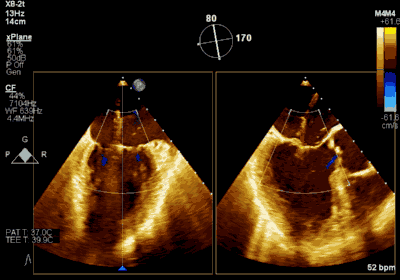

患者为73岁老年男性,既往合并冠心病、持续性心房颤动、肾功能不全病史,此次主诉“反复胸闷气促3月余”入院。诊断:心脏瓣膜病 二尖瓣脱垂伴重度关闭不全 心功能Ⅲ级(NYHA分级)。术前经胸超声心动图示:左房扩大,二尖瓣前后叶冗长、P2脱垂合并重度反流(Type II类 DMR/MR4+)。心脏测值:LA 54 x 58mm,LVD 60mm,EF% 60%,PASP 36mmHg。经食管超声心动图示:二尖瓣环左右径38mm,反流束缩流颈宽度为8.5mm,EROA 0.72cm2(PISA),舒张期二尖瓣口平均跨瓣压差2mmHg。

王焱、王斌教授团队通过术前和台北荣民总医院(Taipei Veterans General Hospital)宋思贤教授进行了详细的讨论并制定了最优的手术策略,同时术中视频连线获得宋思贤教授的技术支持,华体会体育官方网站 超声内科苏茂龙教授负责术中超声心动图引导。患者全麻以后,在经食道超声心动图和X射线引导下,经股静脉入路,将MitraClip瓣膜夹顺利送至二尖瓣前后叶交界中心处,成功捕捉二尖瓣前叶A2和后叶P2,经超声心动图反复确认瓣叶夹持牢固后,测定有效夹持长度11mm,评估反流量降至微量,释放瓣膜夹,超声心动图评估瓣膜夹位置和功能良好,测定左房压降至11/6mmHg,再次评估反流量仍为微量,手术顺利完成。

▲ 术前超声检查显示重度二尖瓣反流

▲ 术后超声检查显示轻度二尖瓣反流